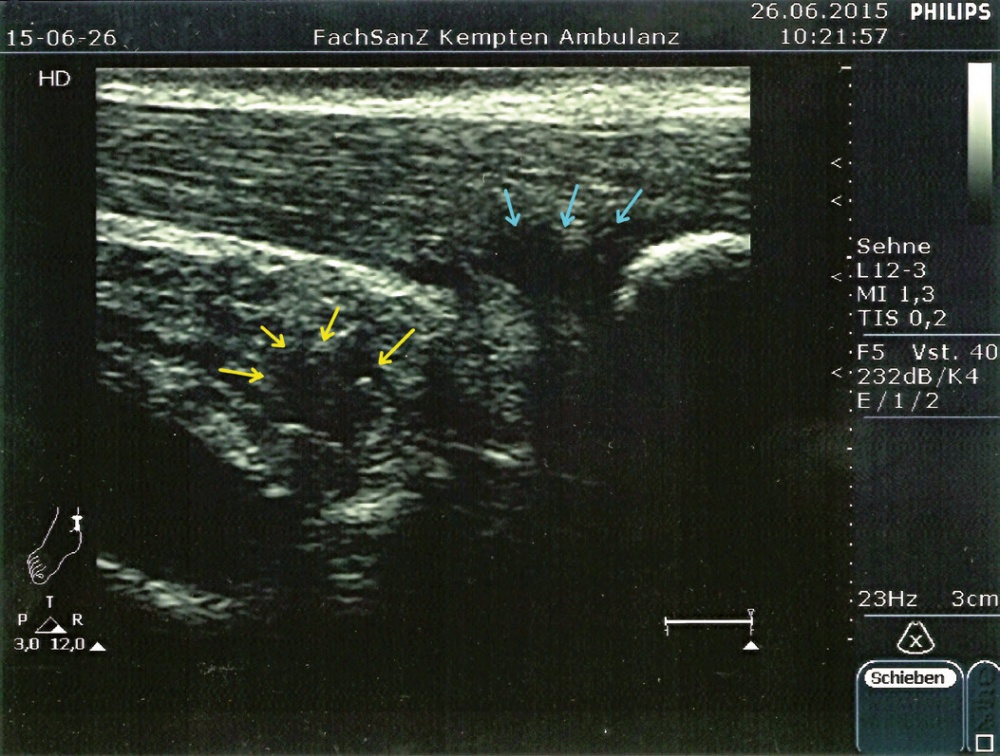

Ein einfacher Test zur Abgrenzung von einer Ruptur der Sehne mit Hämatom, Schwellung und eventuellem Tasten einer Delle ist nach wie vor der Simmonds-Thompson-Test (Plantarflexion des Fußes durch Kompression der Wadenmuskulatur bei intakter Achillessehne). Wie in der Kasuistik beschrieben, erfolgt die weitere Diagnostik mittels Sonographie der Ferse zur Darstellung einer Verdickung, Hypervaskularisation oder Zunahme von echoarmen Arealen. Zudem sollte eine Röntgenuntersuchung durchgeführt werden, um eine mögliche Haglund-Exostose zu detektieren. Eine Kernspintomographie der betroffenen Ferse eignet sich sehr gut zur Darstellung sowohl von strukturellen Veränderungen der Achillessehne, als auch begleitender Entzündungszeichen (siehe Abbildung 3).

Im Rahmen der Diagnostik in der truppenärztlichen Sprechstunde kann neben der obligaten klinischen Untersuchung eine sonographische Darstellung beider Achillessehnen im Seitenvergleich erste Anhalte für die Ursache der Beschwerdesymptomatik liefern.